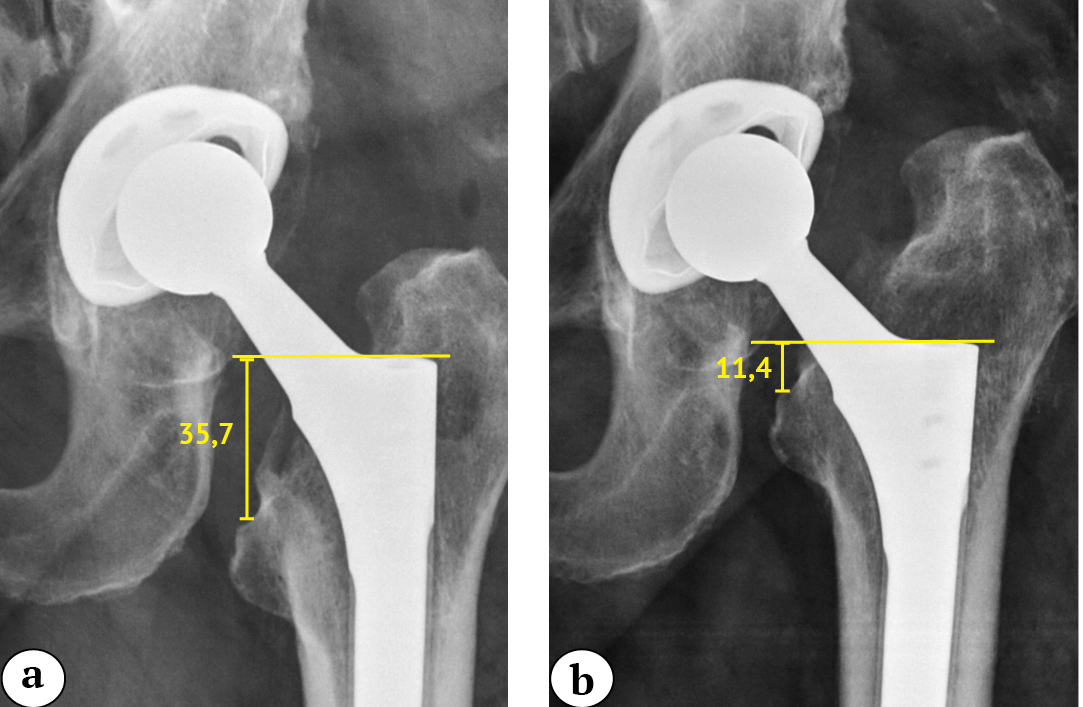

A subsidence of 10 mm or more was considered clinically significant. Bicortical contact was determined as the total length of the direct contact between the cortical plate and the contour of the prosthesis without a radiolucent line on the femur X-ray in the AP view [13, 14] (Fig. 2). Stem varus-valgus alignment was determined by measuring the angle between the lateral periosteal surface of the femoral canal and the longitudinal axis of the stem [19]. The known diameter of the femoral head was used to assess the accuracy of all measurements.

Fig. 2. X-ray images of the right hip of a 50-year-old patient on day 1 after revision surgery: a — the lines indicate the contact between the femoral component and the cortical layer of the femur on the medial and lateral sides; b — the length of the bicortical contact was defined as the total length of the direct contact between the cortical plate and the contour of the prosthesis without a radiolucent line (arrows 1 and 2)